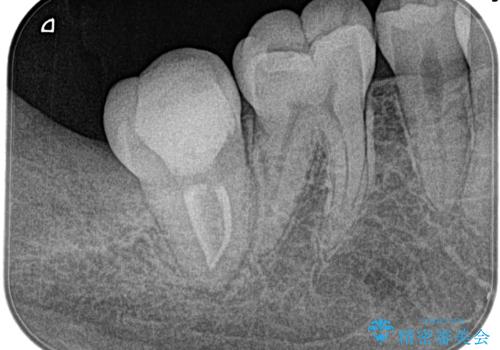

湾曲根管。精密根管治療

担当医 河口智英